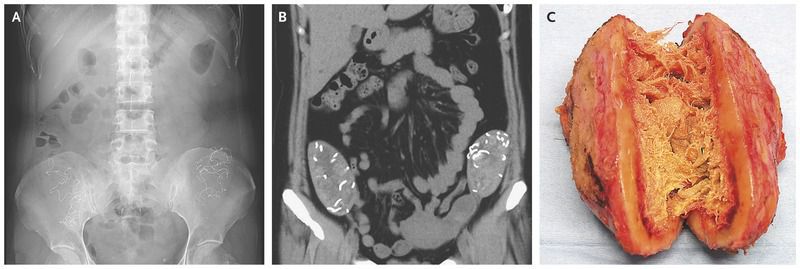

A 42-year-old woman presented to the primary care clinic with a 3-year history of lower abdominal bloating. She had undergone cesarean sections 6 and 9 years earlier. Abdominal palpation revealed nontender masses in the right and left iliac fossae. Abdominal radiographs showed hyperdense, serpiginous, symmetric lesions (Panel A). Computed tomography of the abdomen showed well-defined pelvic masses that contained hyperdense, stringy structures (Panel B). A laparotomy was performed, and two smooth masses were found to be partially adherent to the greater omentum and to the colon; the masses were resected from the paracolic recesses. When the masses were divided in half, gauze sponges encapsulated by thick, fibrous walls (Panel C) and radiopaque barium sulfate strands were observed. A diagnosis of gossypiboma was made. A gossypiboma refers to a foreign object, such as a surgical sponge, left behind in a body cavity after an operation. The use of surgical safety checklists is one method that has been implemented to prevent avoidable complications after surgery through effective communication of the completeness of final sponge and needle counts. The patient recovered uneventfully from the surgery and had complete resolution of the lower abdominal bloating; she was discharged from the hospital 5 days after the surgery.